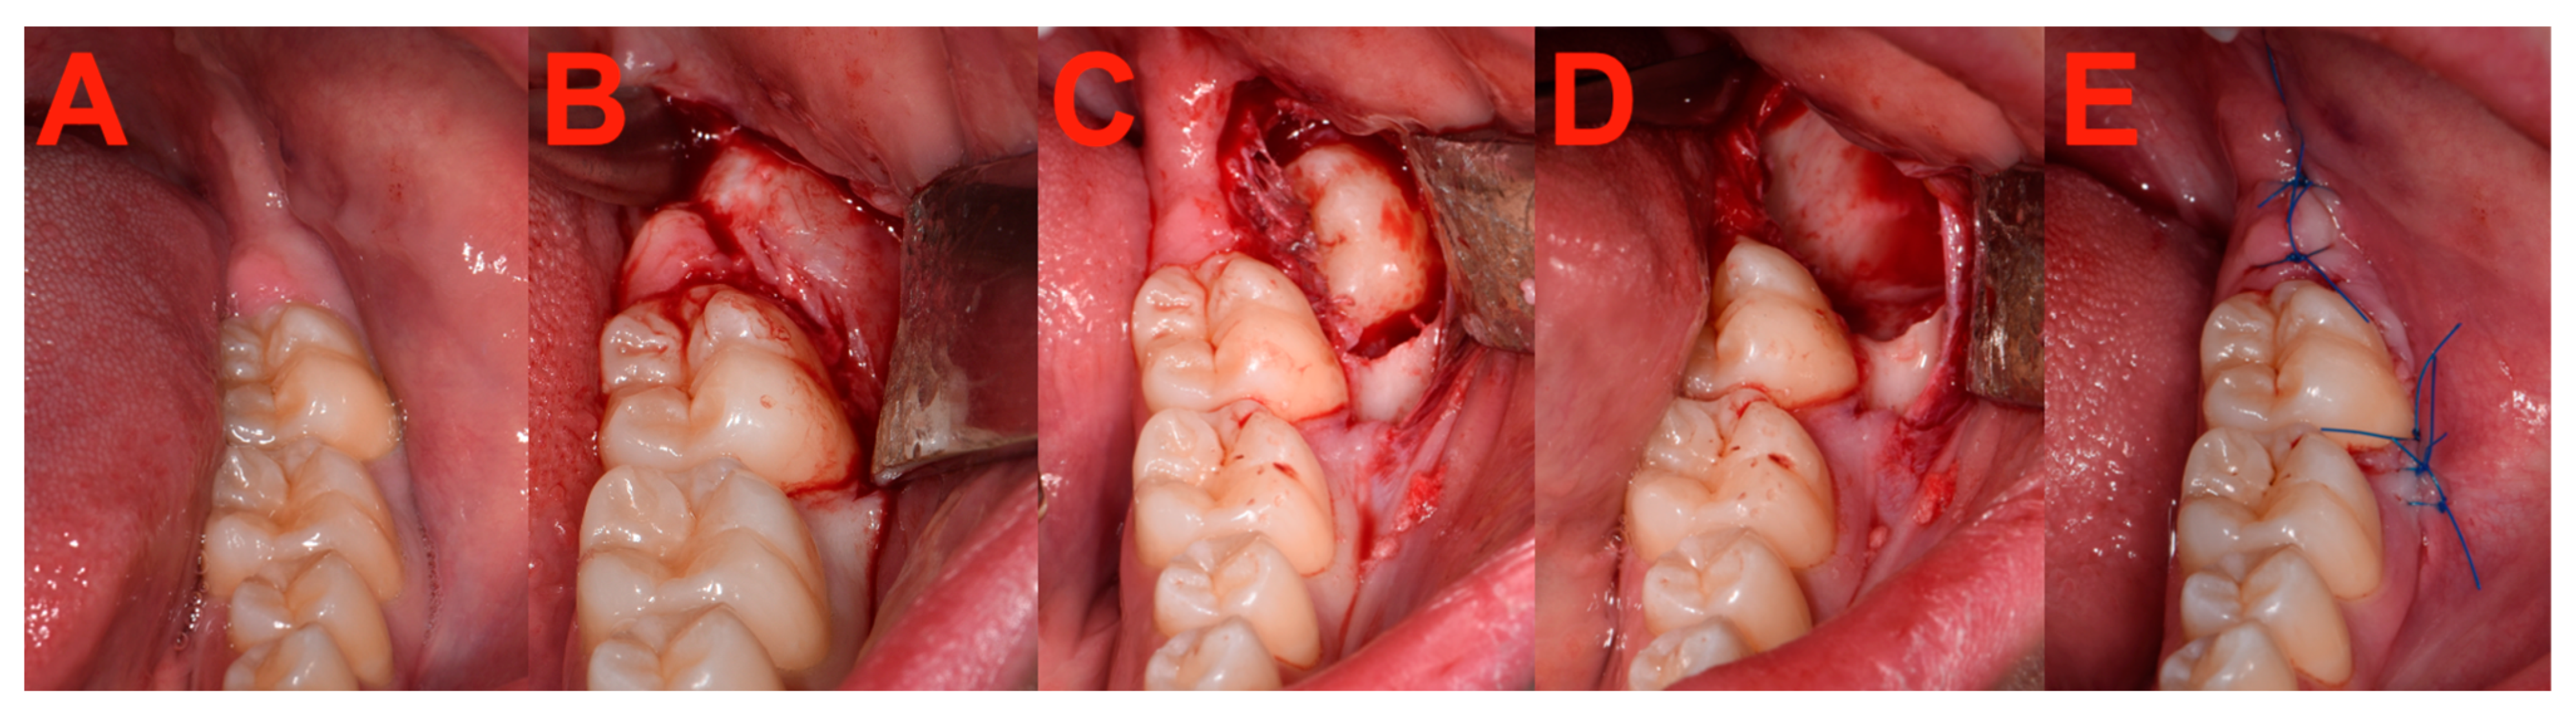

2.7. Surgery